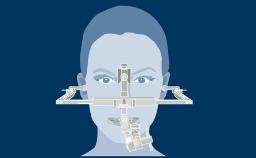

Avaliação Cirúrgica da Região do Implante

Quando os pacientes apresentam inicialmente uma solicitação de tratamento com implante, o fazem com dentes que necessitam de extração ou com dentes ausentes há algum tempo. Embora haja fatores semelhantes que precisam ser avaliados nessas duas situações, um fator adicional a ser considerado quando os dentes estão presentes é o momento ideal para instalar o implante após a extração. Essas considerações são tratadas em um módulo separado sobre o tempo de instalação do implante após a extração do dente. O foco deste módulo é a avaliação cirúrgica da região edêntula após a extração dos dentes e a cicatrização do rebordo.

- descrever os fatores necessários para avaliar os tecidos moles na região do implante

- descrever os fatores necessários para avaliar o osso na região do implante

- descrever a relação entre a prótese planejada e a região do implante